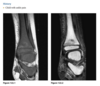

Q

39 yo man fall

Axial T2 fat sat MR - bone contusions in medial patella and lateral femoral condyles (Arrows) with associated tear of medial retinaculum (Arrowhead)

Diagnosis: Acute patellar dislocation relocation

Occurs with internal rotation of femur on fixed and externally rotated femoral condyle - bone contusions on both.

Due to direct impaction, associated with ACL tears.

Radiographs = Lipohaemarthrosis or chip fracture adjacent to donor site of medial facet of patella.

MR findings = Disruption or sprain of the medial retinaculum, lateral patellar tilt or subluxation, lateral femoral condylar and medial patellar osseous contusions. Osteochondral injury to medial patella or lateral femur.